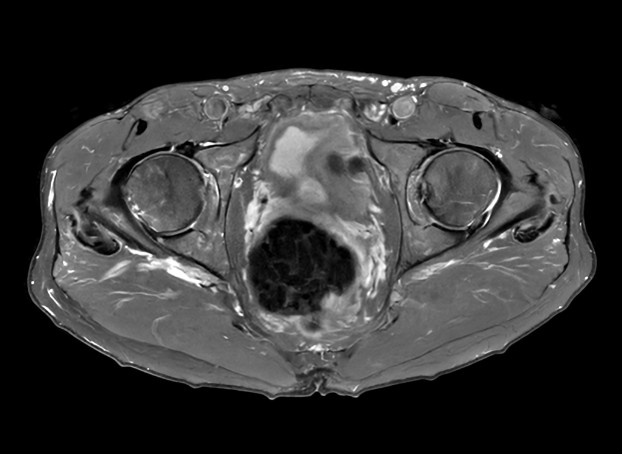

Fast bilateral hips, with SmartSpeed Precise

Used Solution